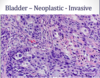

What is this?

With invasive urothelial cancer, the extent of invasion and spread (staging) at the time of initial diagnosis is the most importnat prognostic factor